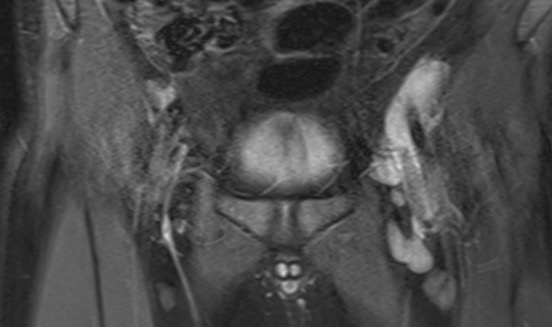

An 8-year-old nonverbal autistic girl presented with her parents to our emergency department with a 6-week history of a progressively worsening limp. At onset, the patient had a mild limp, left-sided...

08/23/2023